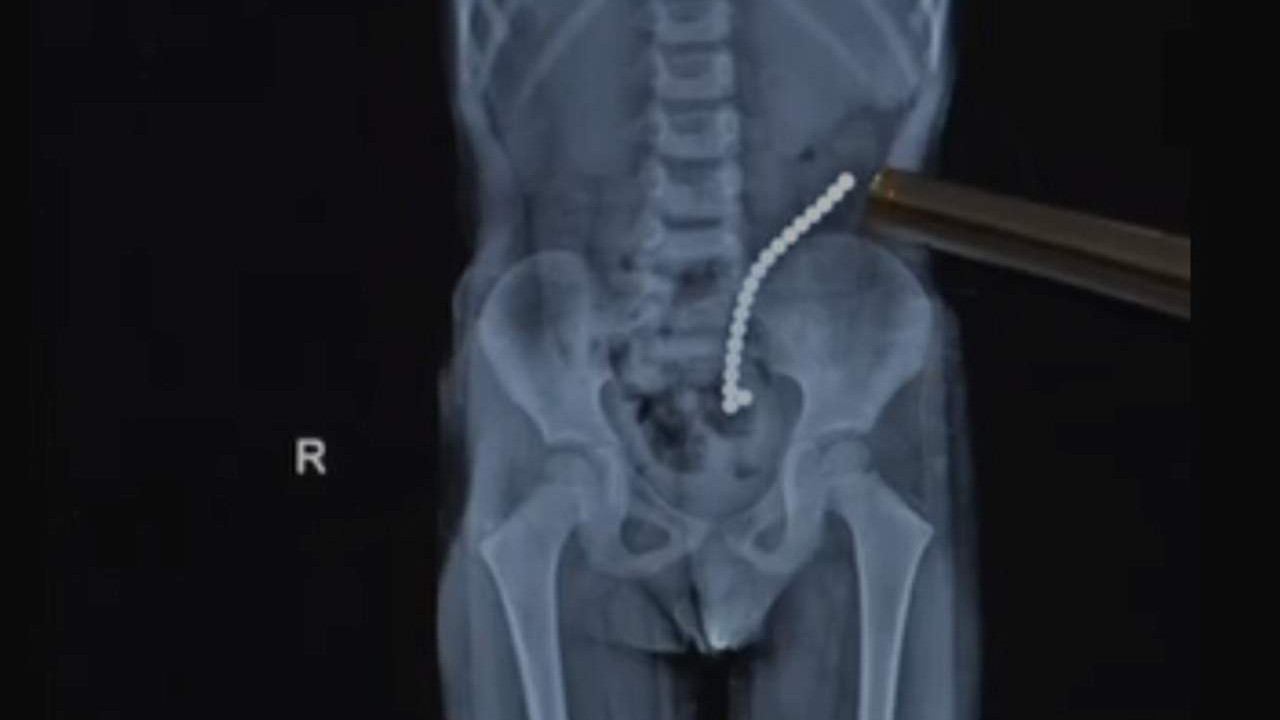

Abone Olİstanbul’da 4 yaşındaki Uras Aslan Aktaş, şiddetli karın ağrısı şikayetiyle ailesi tarafından hastaneye götürüldü. Yapılan müdahalenin ardından küçük çocuğun bağırsağında tam 19 tane ‘neodyum mıknatıs’ tespit edildi.

Uras A., şiddetli karın ağrısı ve kusma şikayeti sonrası ailesi tarafından hastaneye kaldırıldı. Yapılan tetkiklerde küçük çocuğun bağırsağında tam 19 tane oyun amaçlı kullanılan neodyum mıknatıs tespit edildi.

Bağırsağını delen cismi fark eden Çocuk Cerrahisi Uzmanı Prof. Dr. Ali Çay çocuğu ameliyata aldı. 45 dakika süren operasyonda tam 19 tane mıknatıs çıkarıldı. Şaşkın olduğunu söyleyen anne Ayşegül A., “Kahvaltı esnasında çok şiddetli karın ağrısı oldu. Ben tuvalete gitmesini istedim. Ama ağrısı devam etti. Sonra dinlenmesi için yatak odasına götürdüm o esnada bana ‘anne ben mıknatıs yuttum’ dedi” diye konuştu.

Ameliyatı gerçekleştiren Prof. Dr. Ali Çay, “Bu mıknatıslar çok güçlü ve farklı bağırsak segmentlerinde birbirlerine yapışarak bağırsak delinmesine, tıkanıklığa sebep olabiliyorlar. Bizim hastamızın da hem ince bağırsağı birbirine yapıştırmıştı hem kalın bağırsak yapışmıştı. Biz bağırsağın yaralanan kısımlarını onardık. Bu 19 mıknatısı tamamen çıkardık” değerlendirmesinde bulundu.